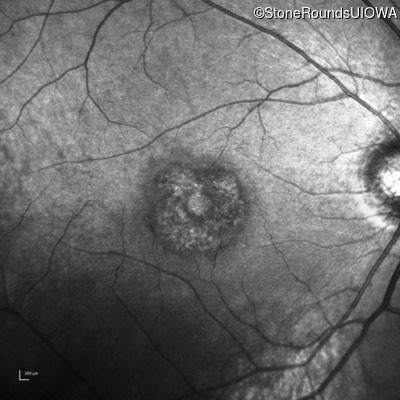

XL Cone and Cone Rod Dystrophy (IA1bi)

Age at visit: 28 years

This 28 year old man has recently noticed some difficulty with fine visual tasks such as tying a fishing lure to a fishing line.

Diagnosis & molecular findings

Disease Gene Allele 1 variant(s) Allele 2 variant(s) Inheritance mode

XL Cone and Cone Rod Dystrophy RPGR Glu1031 del1gA   XL